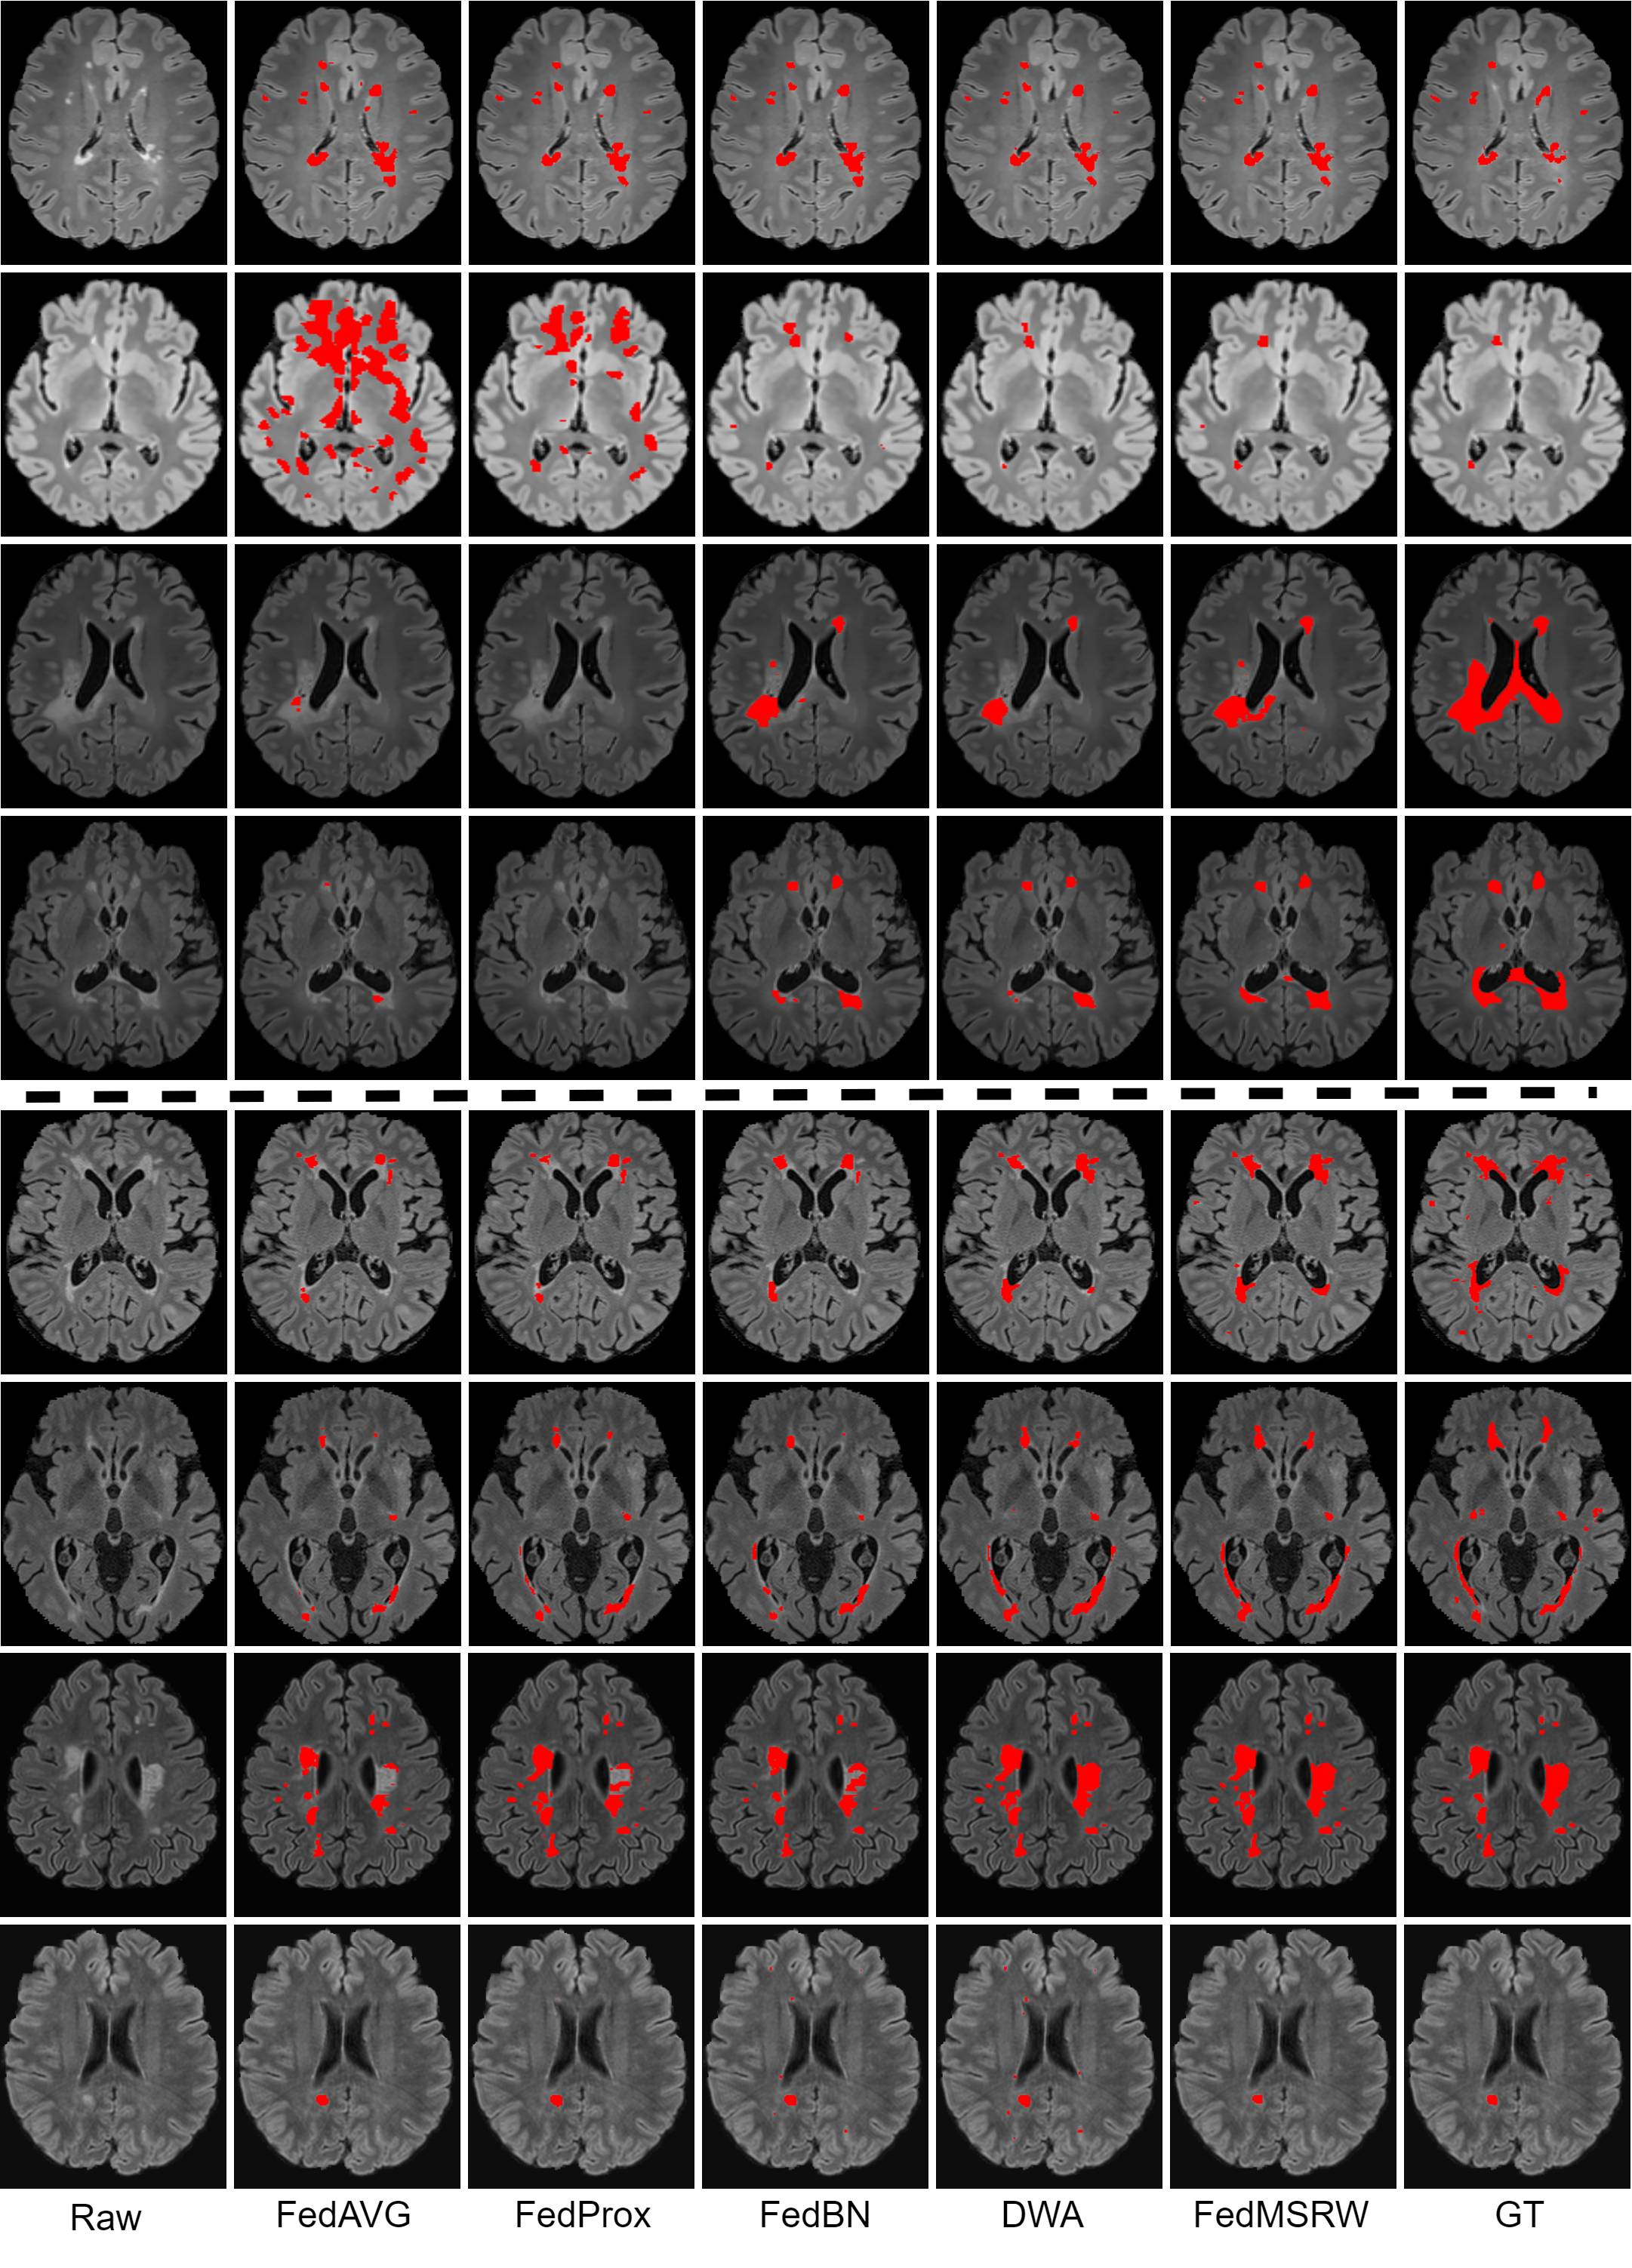

In the first scenario, the MS lesion segmentation experiments were conducted on images from different scanners (from different clinical sites). As shown in Table I, the performance of the typical FedAvg and FedProx methods is worse than the models solely trained with the data in each specific client. For the multi-client MS lesion segmentation dataset, the data distributions for each client are distinct, reflecting variance in hardware and image acquisition protocols. This results in domain bias issues when optimizing the aggregated model on each local client. For MS lesion segmentation task, the foreground objects (i.e. lesions) are almost always small and numerous, with a heterogenous spatial distribution. Subsequently, the domain shifts incur inaccurate segmentation performance for the FedAvg and FedProx methods. By preserving the domain-specific batch normalization in each client, FedBN can alleviate the issue and improve the locally trained models. By further prioritizing inter-client label bias and the distinct model performance, our proposed method outperformed the FedBN and DWA, based on the Dice score at both the case and voxel levels. Our proposed FL method also outperformed centralized training (improved average Dice score and competitive voxel-wise Dice score), which requires each client shares their raw data.

In the second scenario, FL methods were conducted on the in-house and public datasets. First, real-world clinical MS datasets from three different scanners were employed. To further increase the diversity of the FL setting, we include an auxiliary public dataset from another new scanner [47]. The experimental results are presented in Table II. We observed a similar phenomenon as the first scenario, namely that cross-client distribution bias in multi-client MS datasets degrades the collaborative performance of the FedAvg and FedProx, while FedBN achieves much better performance by alleviating the domain bias. However, incorporating the DWA with the FedBN baseline has incurred a severe performance drop. The relatively larger dataset used from each client in the second scenario, which exaggerates client-specific differences in data distribution, may explain this observation. Conversely, FedMSRW, which further considers task-specific factors such as cross-client lesion ratios, and distinct local model MS lesion segmentation ability, outperformed the FedBN under all metrics. Fig. 3 illustrates a visual comparison of FedMSRW with other methods, which further indicates the outstanding segmentation performance of our method.